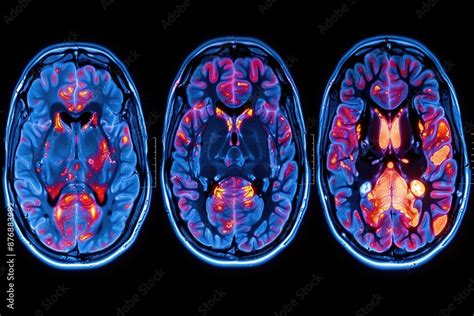

La diagnosi del disturbo bipolare si basa su una valutazione clinica approfondita, spesso integrata da informazioni fornite dai familiari, poiché i pazienti stessi potrebbero non riconoscere o riferire accuratamente i propri sintomi, specialmente durante gli episodi maniacali o ipomaniacali. Non esistono ancora biomarcatori o studi di neuroimaging specifici per la diagnosi.